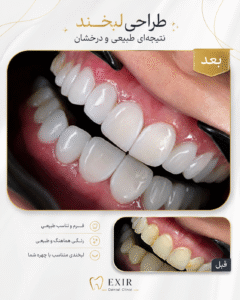

گالری مطب و نمونهکارها

نقش متخصص بیماریهای دهان در درمان زیبایی چیست؟

جلوگیری از درمانی که به سلامت آسیب بزند.

چه زمانی نباید درمان زیبایی انجام داد؟

وقتی هنوز علت اصلی مشکل مشخص نشده است.